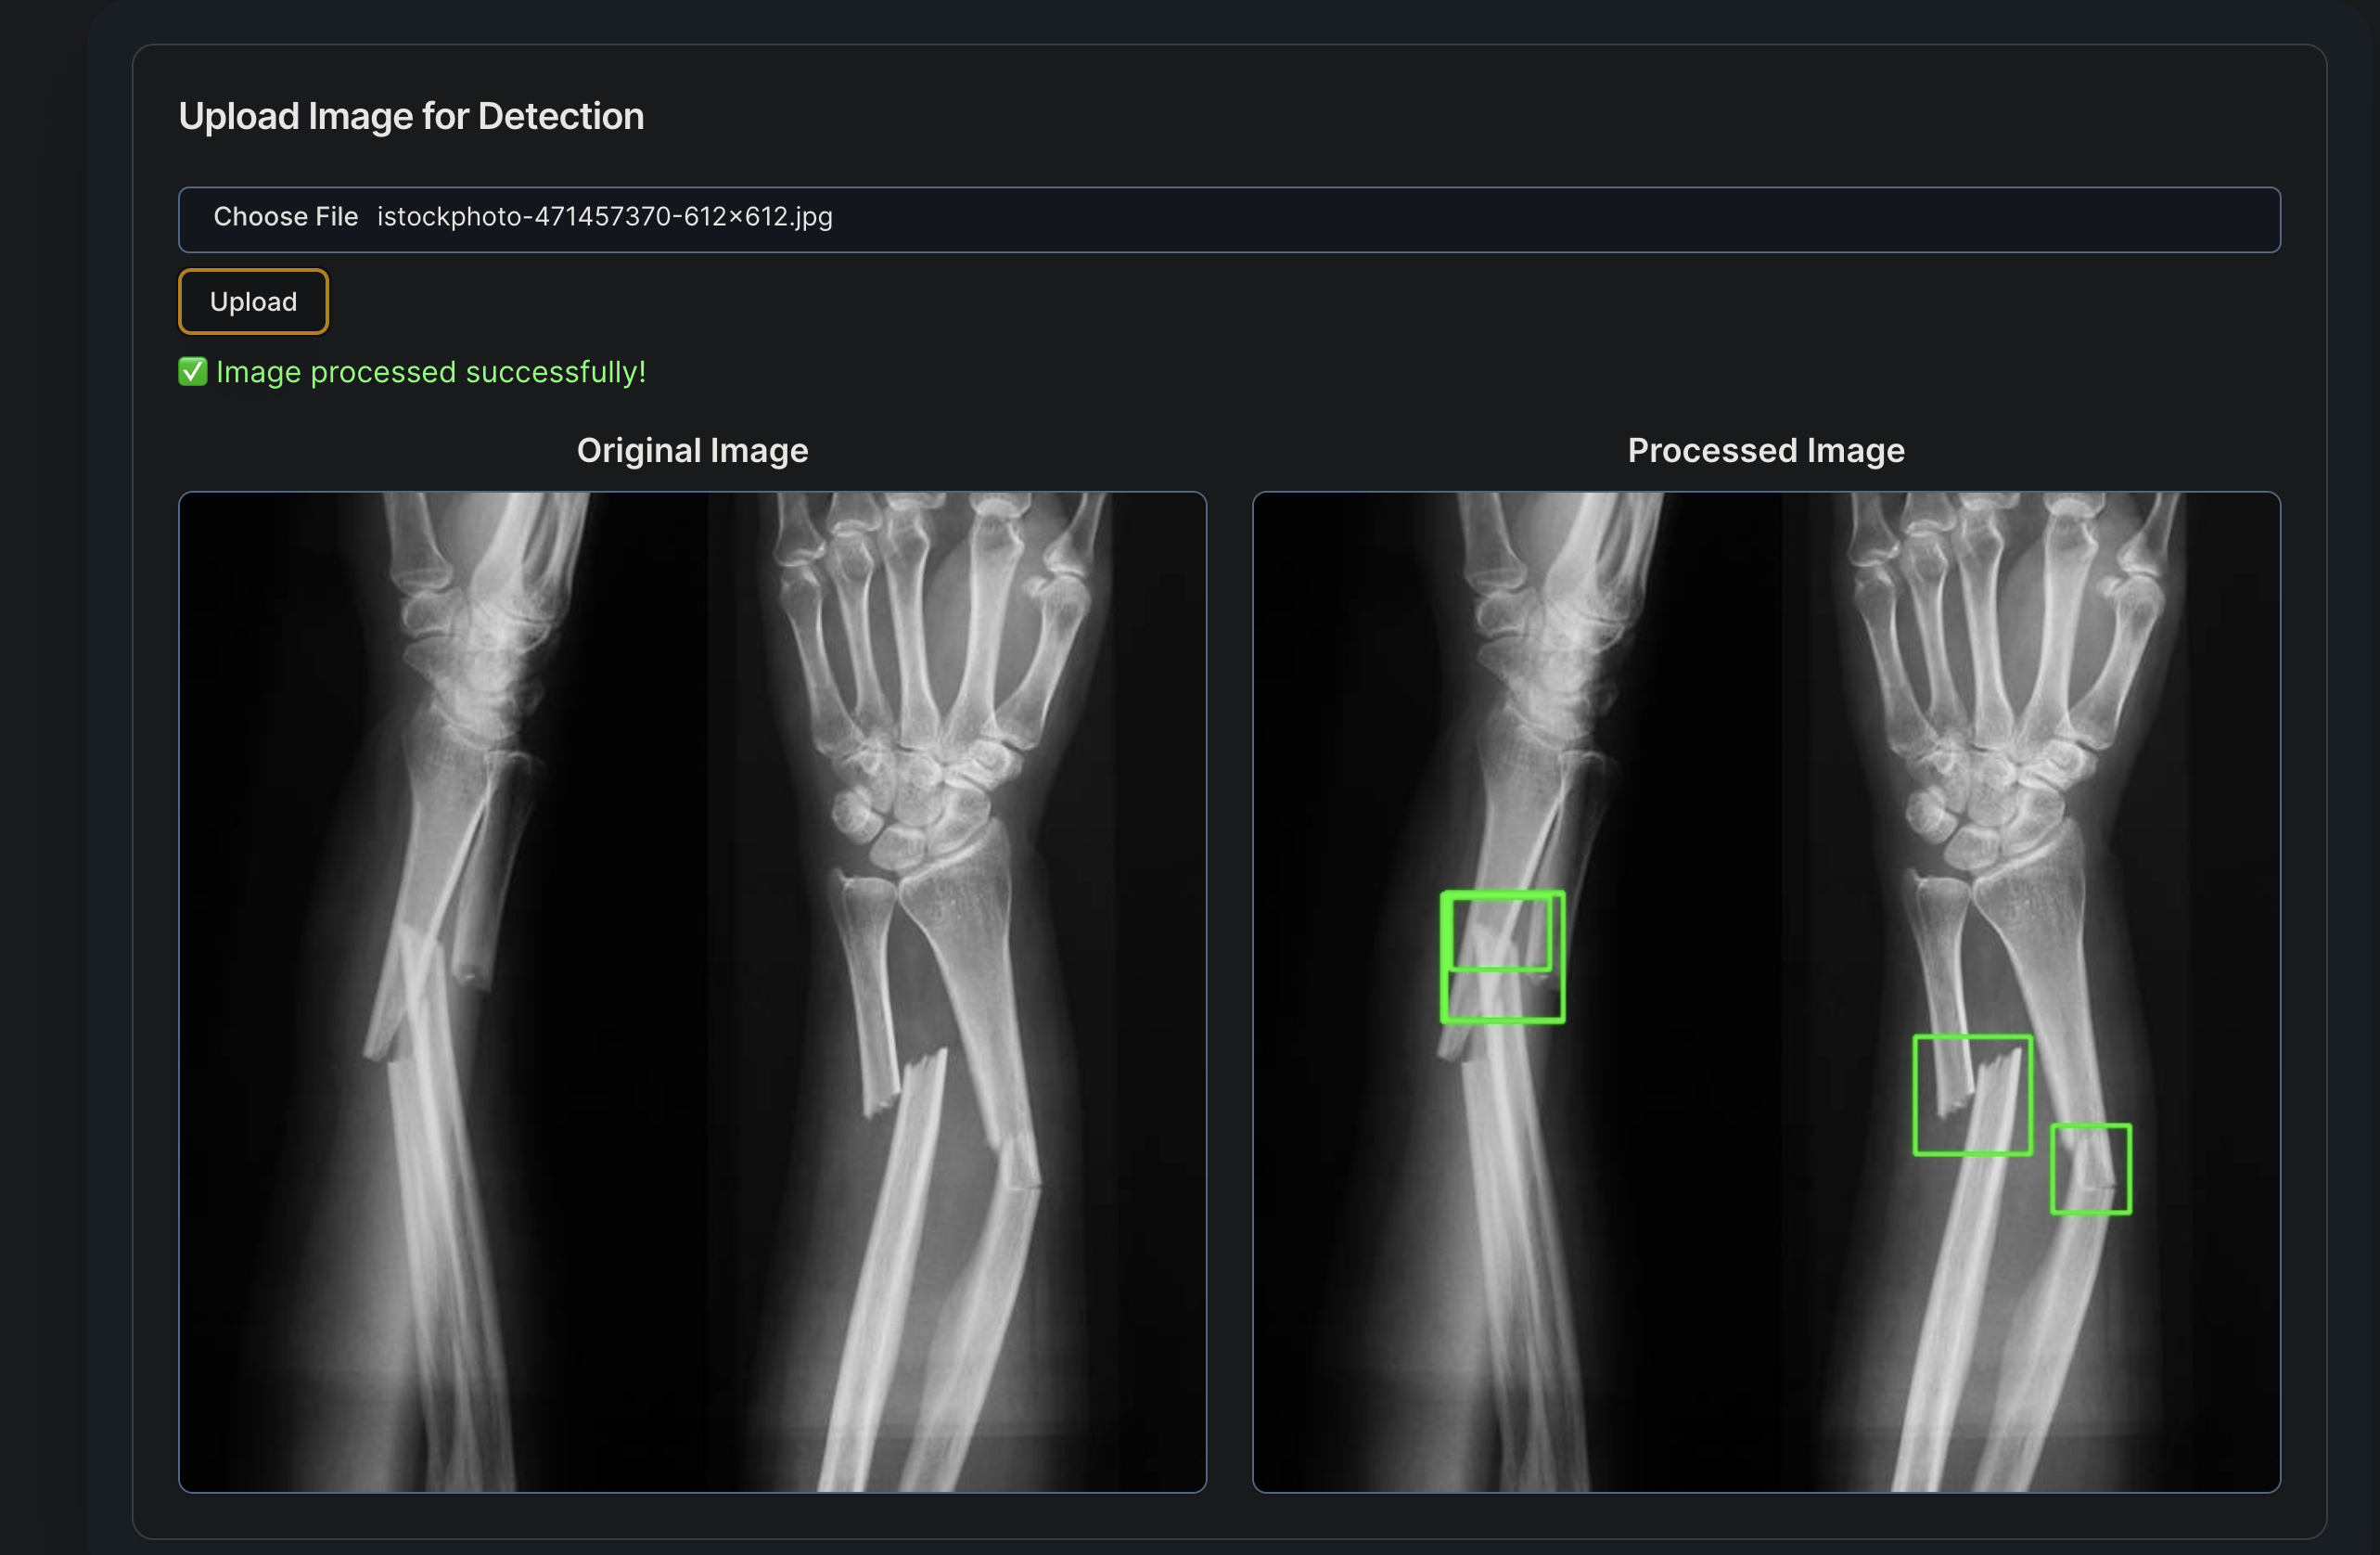

4. Fracture Detection: Trained a Yolov11 model on a fracture dataset and used OpenCV to run detection on uploaded images of patient x-rays.

• Integrated fracture detection into the front end